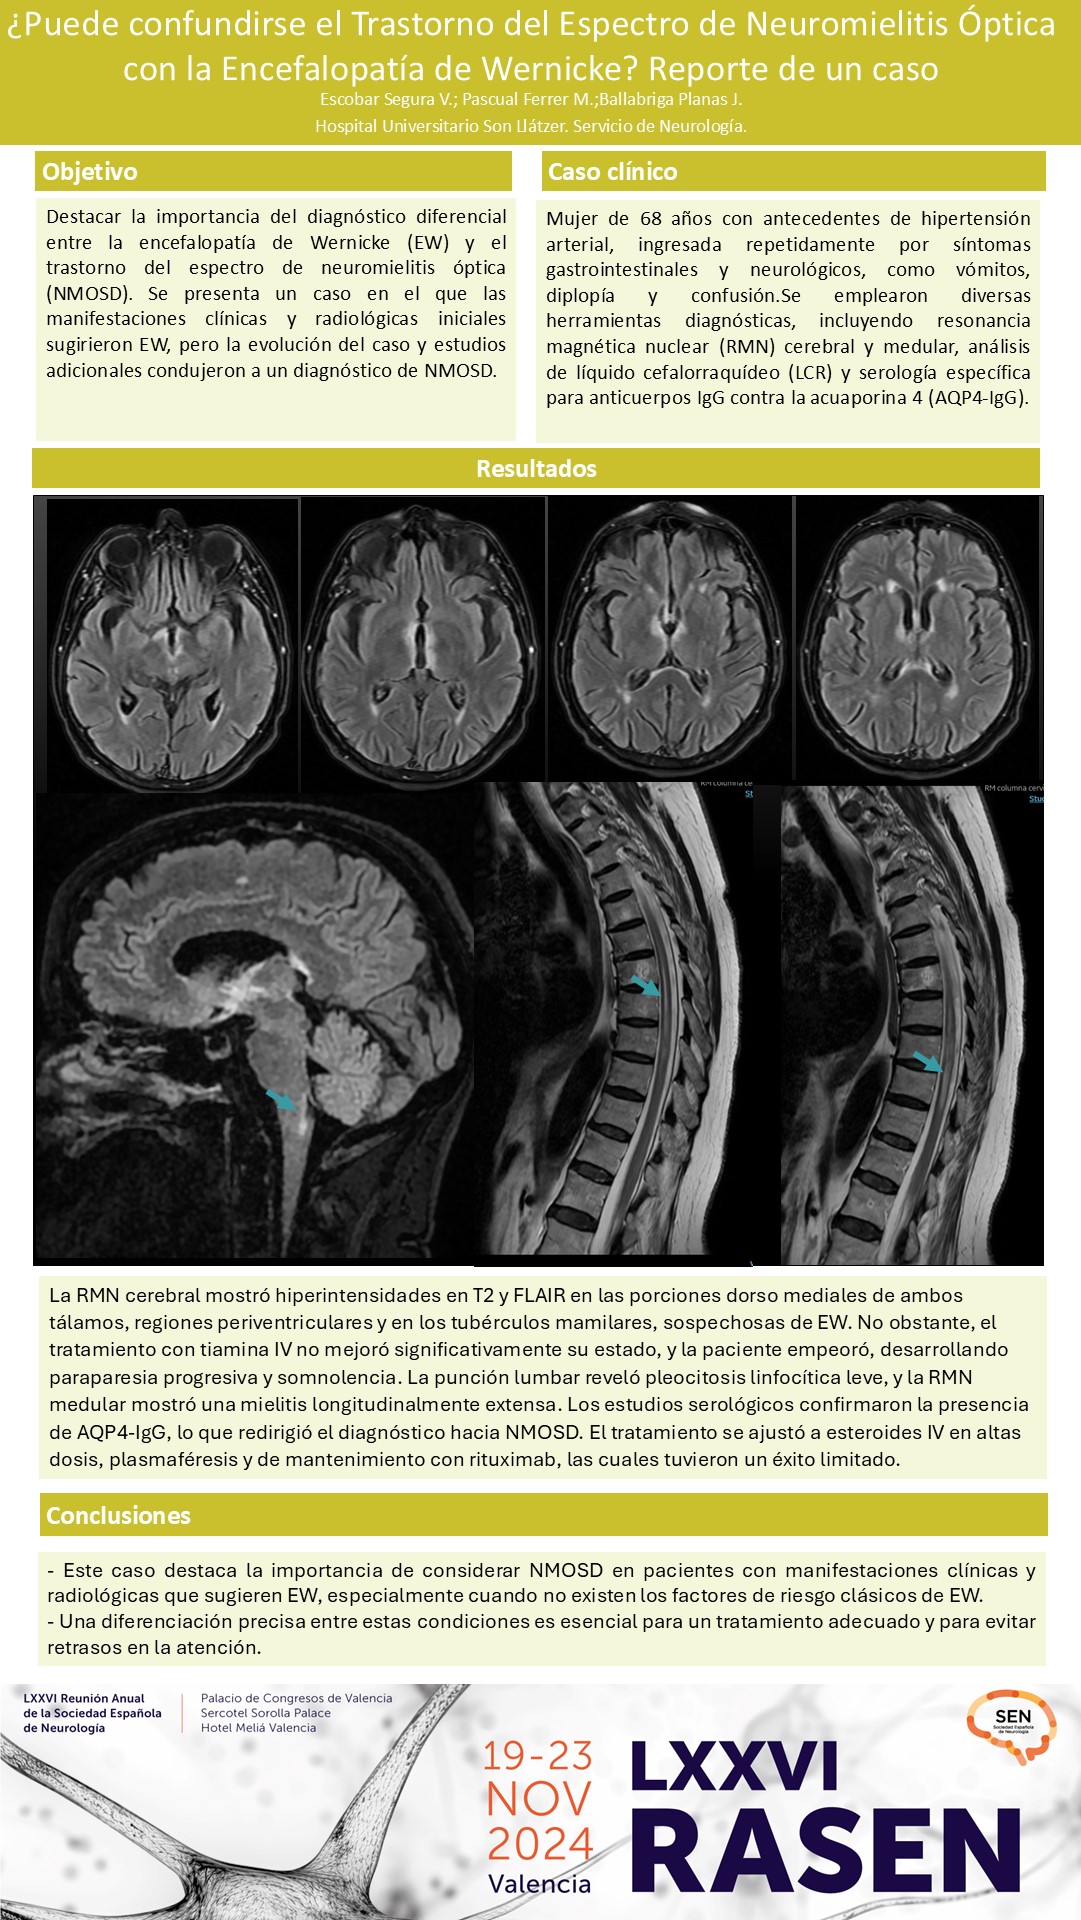

Escobar Segura, Viviana

Servicio de Neurología. Hospital Son Llàtzer